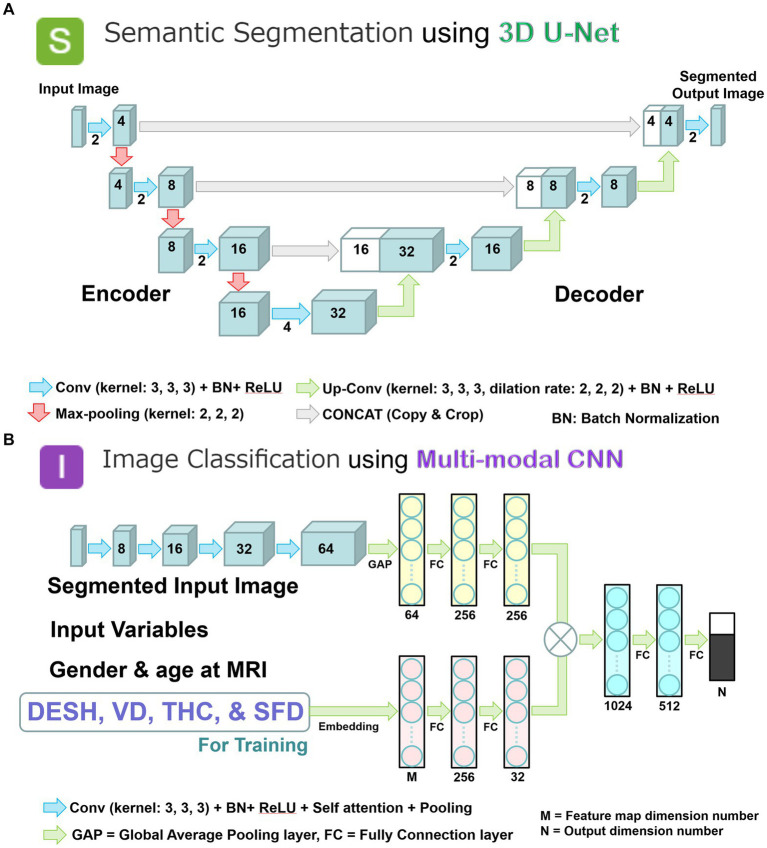

Deep learning tasks

We combined two deep learning models to employ a two-step method of automatic detection of DESH with segmented volumes and indices. In the first step, the volumetric semantic segmentation task employed a 3D U-Net with four layers, consisting of 3D convolution with a batch normalization layer, ReLU activation layer, max pooling layer, and 3D up-convolution layer (Figure 3A). Signal values were normalized by percentile (minimum 0.05, maximum 0.95) as a preprocessing step. To compensate for voxel detail, feature maps are concatenated from each encoding layer of feature extraction by downsampling to the corresponding decoding layer of feature assignment by upsampling. In the second step, the image classification task employed a multimodal convolutional neural network (CNN) (Figure 3B). As ground truth labels for the image classification task, the presence or absence of DESH, VD, THC, and SFD was determined by a neurosurgeon and a radiologist, both experts in imaging diagnosis of Hakim disease, through consensus reading. Input data included the presence of DESH, VD, THC, and SFD, in addition to age at MRI, gender, and the same image masks used in the first step volumetric semantic segmentation task (Figure 3B). For the output of the image classification task, the intracranial CSF space mask was used to determine the presence or absence of DESH, and the masks for the total ventricle, high-convexity SAS, and Sylvian fissure and basal cistern were used to determine the presence of VD, THC, and SFD, respectively. In the embedding layer, all input variables were transformed into feature maps. At the end of the last convolutional layer, the final feature maps were fed to a softmax activation function to generate a probability score for each class. Image intensities of input images were normalized to [0, 1] by their maximum and minimum values. Augmentations including rotation, scaling, and translation of the input image masks were made to improve generalizability and accuracy in the semantic segmentation and image classification tasks. The generalizability of these augmentations would help reduce effects from differences between manufacturers, imaging protocols or individuals, and increase the robustness of our AI model.